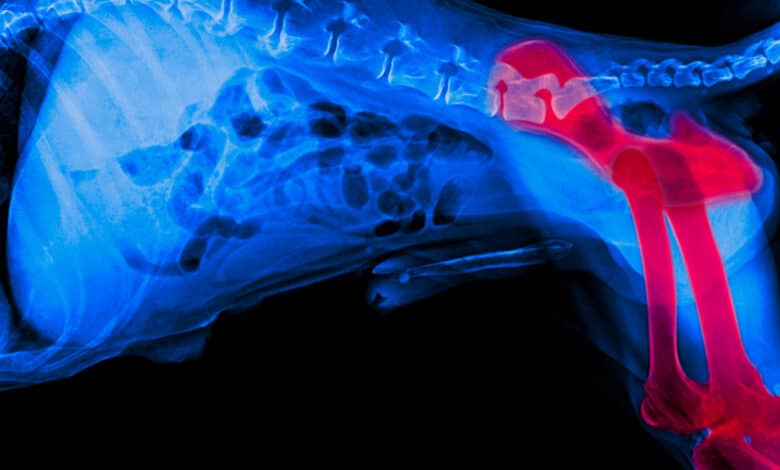

La displasia dell’anca nel cane è una patologia degenerativa dei tessuti ossei del bacino che colpisce sopratutto le razze medie, grandi e giganti. Essa consiste in una malformazione dell’articolazione coxo-femorale dell’arto e può essere diagnosticata fin dalla giovane età con un esame radiografico e veterinario accurato.

Tale malformazione consiste in una sorta di disallineamento tra la cavità articolare dell’anca e la testa del femore. Questa ‘incongruenza’ causa infiammazioni, lussazioni e indebolimento dei tessuti periarticolari che col tempo tendono a peggiorare. La patologia evolve solitamente con la formazione di artrosi cronica progressiva, mono o bilaterale.

L’OFA (Orthopedic Foundation for Animals) individua 4 stadi degenerativi della displasia dell’anca nel cane. Essi corrispondono, di fatto, ai diversi stadi in cui la malattia evolve:

- I Grado: sublussazione di lieve entità con alterazioni degenerative piuttosto scarse e modesto dolore.

- II Grado: sublussazione laterale accentuata della testa femorale (20-25%)

- III Grado: testa femorale fuori dell’acetabolo (50-75%). Fenomeni degenerativi molto marcati.

- IV Grado: dislocazione completa della testa femorale e appiattimento del bordo acetabolare e della testa del femore.

Come più volte sottolineato, è fondamentale una diagnosi precoce della patologia che può essere accertata attraverso uno studio radiografico già tra i 4 ed i 6 mesi di vita del cane. Lo studio in questione consente di valutare il grado di predisposizione genetica dell’esemplare e, in caso di necessità, intervenire chirurgicamente prima ancora che la malattia faccia il suo esordio.